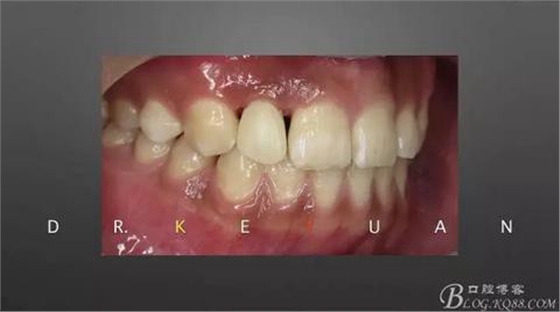

12、粘接后即刻(齦緣的高度略有差異,這應(yīng)該可以說明冠延長術(shù)和正畸牽引的效果差異)

13、術(shù)前術(shù)后對比

14、術(shù)后微笑照